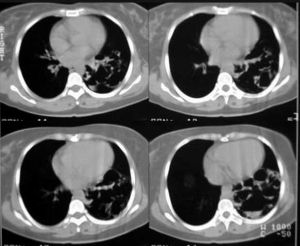

右肺上葉支氣管囊腫CT1.單個液氣囊腫:最為常見,囊腫大小不一,可見圓形薄壁囊腫,內有液面。此種囊腫的特點是囊壁菲薄,鄰近肺組織無炎性浸潤病變,纖維性變不多,需與肺膿腫,肺結核空洞和肺包蟲囊腫鑑別。在X線上表現肺膿腫壁較厚,周圍炎症表現明顯,肺結核空洞則有較長病史,周圍有結核衛星灶。肺包蟲囊腫有流行病學的地區特點、生活史和職業史、血像、皮內試驗等有助於鑑別。

左下肺多發支氣管肺囊腫並感染在成人,多數非感染性囊腫可無症狀,胸片偶然發現,有症狀者,咯血最常見,這幾乎均與囊腫內或周圍感染有關,如囊腫與支氣管的交通呈活瓣機制,可使囊腫迅速增大。

典型的放射學表現為邊緣清楚、單發、圓形或橢圓形陰影,位於下葉的中三分之一,陰影的大小和形狀很少隨時間而改變,雖然也可見到數年後稍有增大者,75%於支氣管相通,並引起感染,相通後含氣,這類感染病人可因周圍炎性組織而使陰影邊緣變得模糊,而囊腫的陰影特性只有在感染消退後才能顯出。